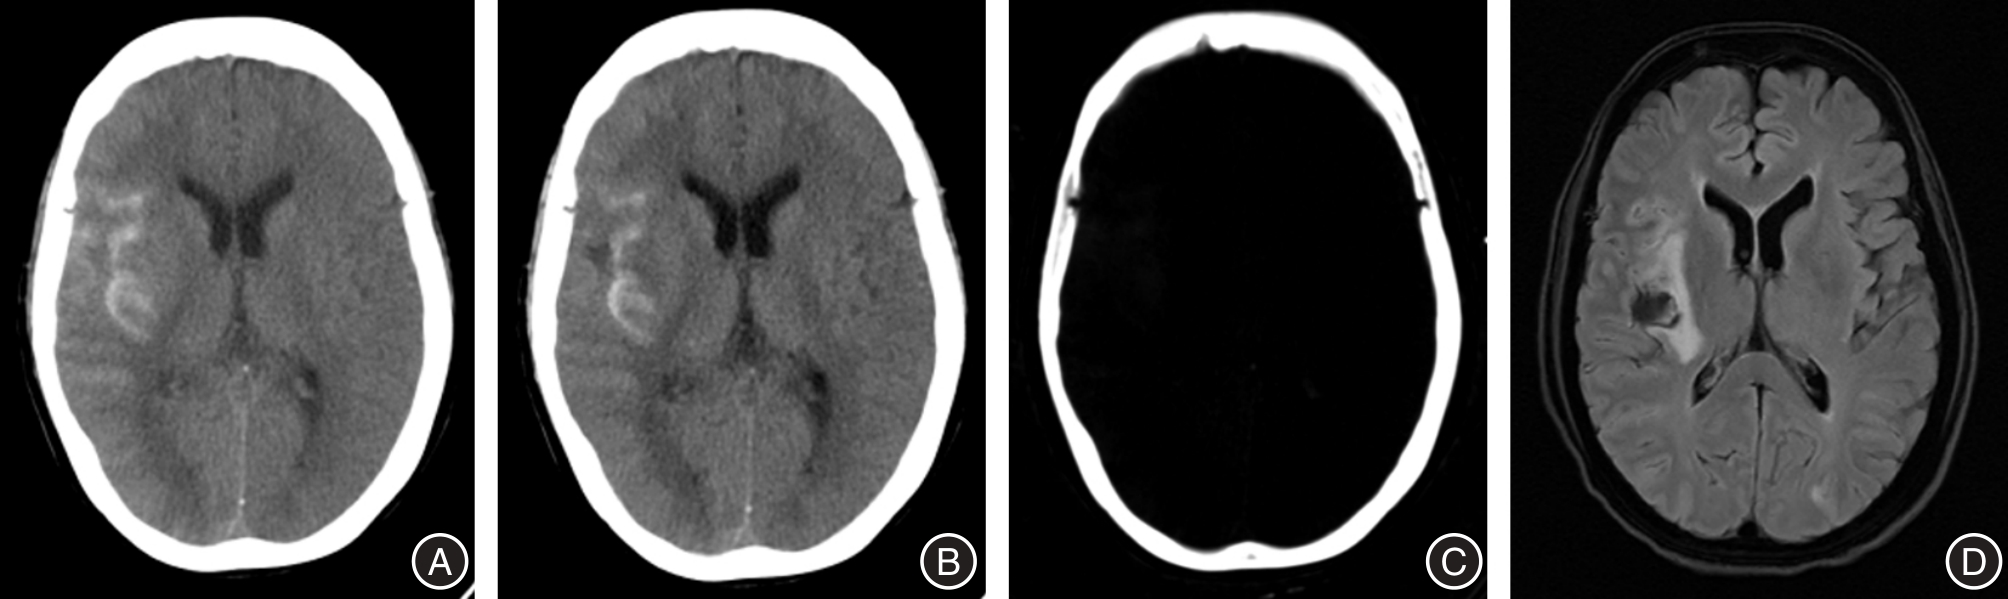

GULKO E, ALI S, GOMES W, et al. Differentiation of hemorrhage from contrast enhancement using dual-layer spectral CT in patients transferred for acute stroke[J]. Clin Imag, 2020, 69: 75-78. doi:10.1016/j.clinimag.2020.06.046

BERNSEN M L E, VEENDRICK P B, MARTENS J M, et al. Initial experience with dual-layer detector spectral CT for diagnosis of blood or contrast after endovascular treatment for ischemic stroke[J]. Neuroradiol, 2022, 64(1): 69-76. doi:10.1007/s00234-021-02736-5

RIEDERER I, FINGERLE A A, ZIMMER C, et al. Potential of dual-layer spectral CT for the differentiation between hemorrhage and iodinated contrast medium in the brain after endovascular treatment of ischemic stroke patients[J]. Clin Imaging, 2021, 79: 158-164. doi:10.1016/j.clinimag.2021.04.020